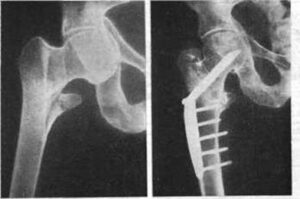

Ложный сустав после перелома шейки бедра или голени

Псевдосустав после перелома — одна из самых частых и сложных патологий. В данном случае мы имеем дело с костной мозолью, которая не имеет четких границ. Это явление может сопровождать переломы любых суставов. Однако чаще всего псевдосустав возникает при травмах голени и переломах бедра. Причины образования ложного сустава Основная причина образования псевдосустава — ненадежная фиксация сломанных …